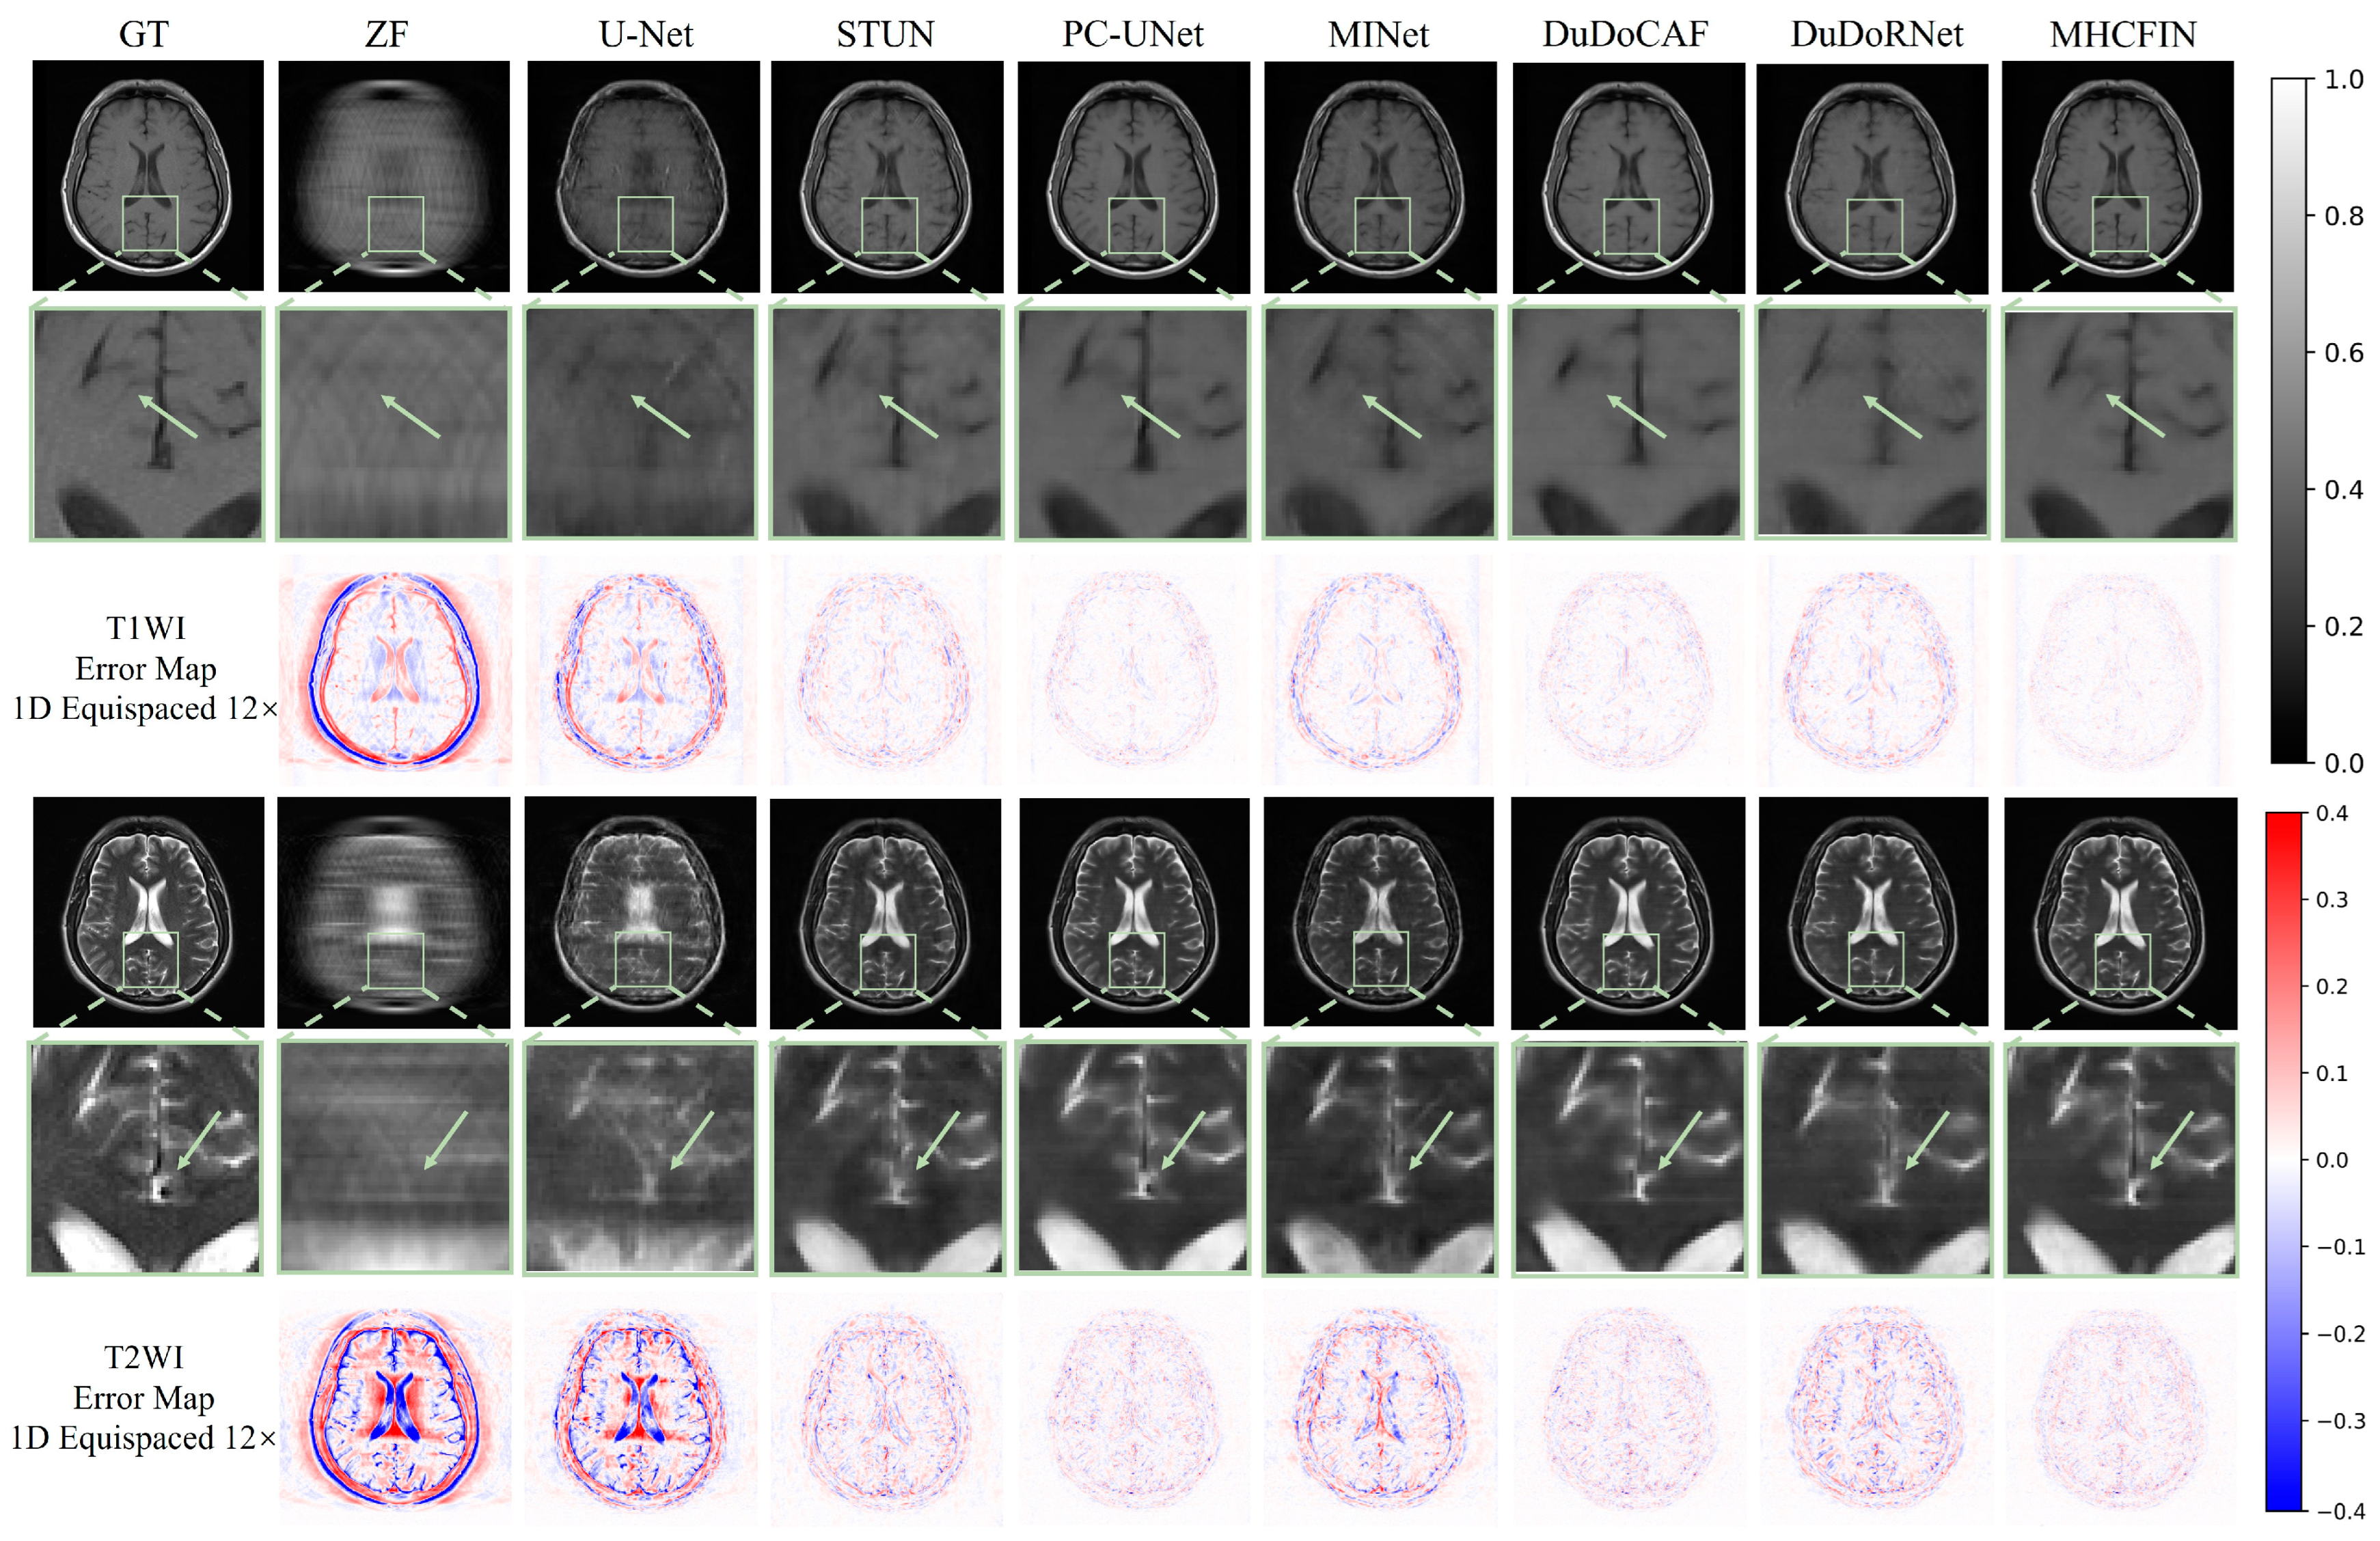

5.2. Qualitative Results

| 1D Equispaced 12× (Mean (Standard)) | ||||||

| ZF | 19.783 (1.024) | 0.511 (0.072) | 0.365 (0.055) | 19.504 (0.925) | 0.560 (0.041) | 0.401 (0.035) |

| U-Net [51] | 26.172 (1.070) | 0.732 (0.052) | 0.175 (0.031) | 22.314 (1.256) | 0.722 (0.068) | 0.292 (0.040) |

| STUN [15] | 31.699 (1.396) | 0.835 (0.045) | 0.094 (0.024) | 28.170 (1.483) | 0.859 (0.058) | 0.149 (0.027) |

| PC-UNet [47] | 34.906 (1.479) | 0.911 (0.032) | 0.065 (0.015) | 32.020 (1.027) | 0.921 (0.031) | 0.095 (0.010) |

| MINet [49] | 30.079 (1.765) | 0.833 (0.047) | 0.114 (0.036) | 26.182 (1.870) | 0.837 (0.072) | 0.190 (0.046) |

| DuDoCAF [27] | 34.481 (1.017) | 0.911 (0.020) | 0.067 (0.012) | 31.828 (0.835) | 0.917 (0.025) | 0.097 (0.008) |

| DuDoRNet [14] | 31.753 (1.336) | 0.858 (0.034) | 0.093 (0.023) | 28.449 (0.911) | 0.869 (0.039) | 0.143 (0.013) |

| MHCFIN | 36.277 (1.013) | 0.913 (0.031) | 0.055 (0.010) | 32.302 (0.890) | 0.922 (0.030) | 0.092 (0.008) |